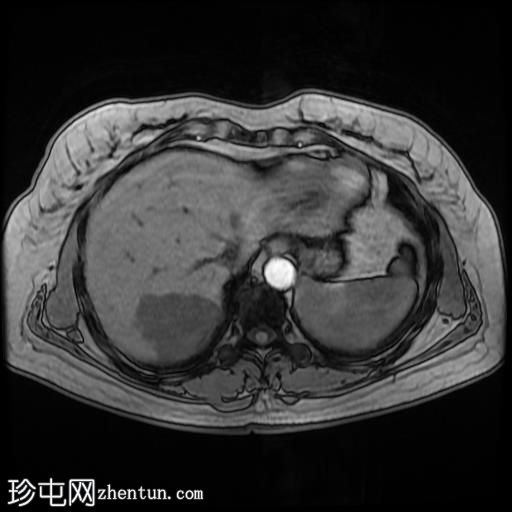

轴位T1加权像

GE IPOP序列

肝脏第7段可见一边界清晰的分叶状肿块。T1加权像呈低信号,T2/T2脂肪抑制序列呈高信号,动脉期呈不连续结节状周边强化,门静脉期呈向心性强化,延迟期完全强化。DWI序列呈高信号,ADC值呈混合信号。